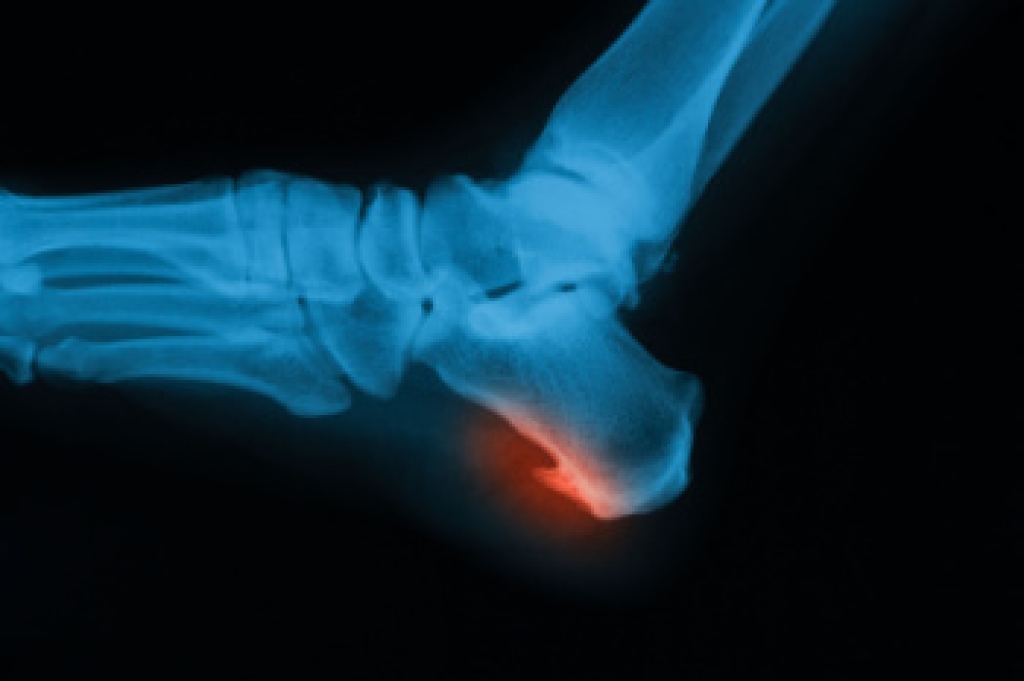

Heel spurs are bony growths that form on the calcaneus, or heel bone, after long-term stress or irritation. These spurs often develop when repeated pulling from tight soft tissue at the back of the ankle places strain on the bone. Eventually, the body responds by laying down excess calcium, creating a pointed growth that looks like a spur. Heel spurs can form underneath the heel or at the back, sometimes causing a visible lump. Symptoms include sharp pain with the first steps in the morning, a lingering dull ache during the day, stiffness, numbness, or thickened skin from friction. A podiatrist can assess foot alignment, evaluate walking patterns, and order X-rays to confirm the diagnosis. Treatment options include custom orthotics, bracing, anti-inflammatory care, or surgery when necessary. If you have pain from heel spurs that affect daily activities, it is suggested that you make an appointment with a podiatrist for an exam, diagnosis, and treatment.

Heel spurs are formed by calcium deposits on the back of the foot where the heel is. This can also be caused by small fragments of bone breaking off one section of the foot, attaching onto the back of the foot. Heel spurs can also be bone growth on the back of the foot and may grow in the direction of the arch of the foot.